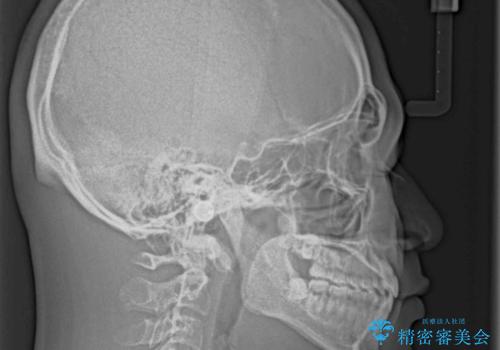

空隙歯列を閉じる 舌のトレーニングとワイヤー矯正

- 上下前歯の隙間を気にして来院された患者様です。

飲み込みや話をするときに舌を突出させる癖が強くあり、それが原因でスペースが空いていました。

舌癖を改善するためのトレーニングを行いながら、ワイヤー装置を用いて前歯の隙間を閉じていくこととしました。

舌の突出癖がなかなか改善されず、治療期間は当初予定よりも大分長くなりました。

装置除去を予定していた日に、油断されたのか1mmほどのスペースを作ってしまったため、除去が3ヶ月延長されたことで、舌のトレーニングの重要性を理解していただきました。

装置除去後もトレーニングを継続されているようで、後戻りによるスペースは今のところ認められておりません。